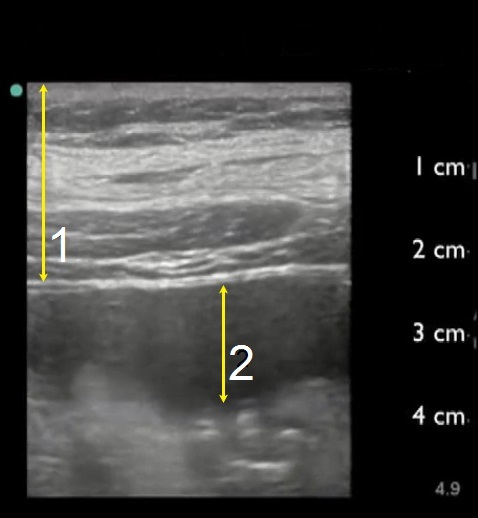

Abdominal Wall

Ascites (safety zone)